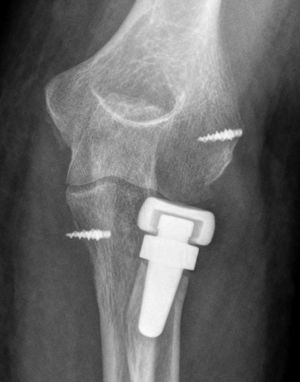

A total of 17 patients (40%) presented signs of radiolucency around the prosthesis stem, in most cases located in the proximal area of the prosthetic neck. Most of these (15) did not report any specific pain symptoms over the radial head. We also observed the presence of capitellar osteopenia in 6 patients (Fig. 2), although we could not demonstrate the implantation of an oversized prosthesis, through the existence of parallelism in the ulnohumeral joint in the elbow anteroposterior radiograph, in any of them.

Three of the 9 patients (33%) who presented complications required a new surgical intervention for the treatment of their lesions. In one case, the patient suffered a dislocation of the prosthesis in the immediate postoperative period, which was treated by replacing the implant with another of a smaller size. The other 2 cases corresponded to painful aseptic loosening, with radiolucency around the entire prosthetic stem, requiring revision surgery. One was a patient who had suffered a “terrible triad” and who developed pain symptoms in the radial side of the elbow, with periprosthetic osteolysis, heterotopic ossifications and severe ulnohumeral osteoarthritis (or arthrosis) 4 years after the surgery (Fig. 3A and B). The patient was reintervened, with radial implant resection arthroplasty which led to the cessation of pain symptoms and a good functional result (Fig. 4A and B). The initial lesion in the other patient was an Essex-Lopresti fracture-dislocation which began with pain in the radial head, associated with signs of radiolucency around the prosthetic stem, 3 years after the initial surgery. The reoperation consisted of replacement with a new cemented prosthesis, leading to cessation of symptoms in the early postoperative period.

The appearance of radiolucency around the prosthesis was less frequent than with movable stem implants, which function as spacers, and was not usually associated with the presence of symptoms.18,30 However, in our study there were 2 cases of reoperation due to pain linked to prosthetic loosening, documented by plain radiography. These findings have already been highlighted in other publications,32 where osteolysis around the prosthetic stem was the most common radiological finding, resulting painful with moderate to severe intensity in all patients suffering from it. Osteolysis appeared to be less common in bipolar and monopolar prostheses with fixed stems, possibly due to lesser stress being transmitted. The absence of suspicious clinical data and negative analyses (erythrocyte sedimentation rate [ESR], C-reactive protein [CRP]) ruled out an association of this radiological finding with the presence of low-grade infection, so there was no need to extend the study with bone scintigraphy scans or joint arthrocentesis in patients with painless osteolysis. Cultures from the 2 replaced prostheses were negative.